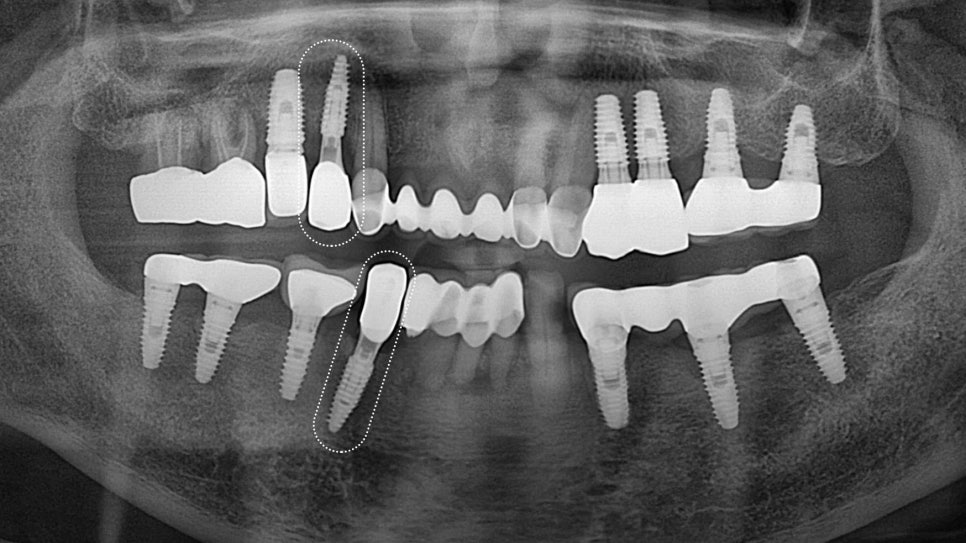

「 이러한 병변들이 광범위하게 진행되어

치아의 보존이 불가능한 경우,

발치가 불가피한 선택이 됩니다. 」

→ 한 연구에 따르면,

발치 후 치아 발치 후 처음 3개월 동안

영향을 받은 경조직과 연조직의

약 3분의 2가 어느 정도 흡수됩니다.

이러한 변화는 향후 임플란트 치료에

상당한 제약을 가할 수 있습니다.

치조골의 흡수는

임플란트의 안정적인 식립을 어렵게 만들며,

특히 전치부의 경우

심미적인 결과에도 악영향을 미칠 수 있습니다.

따라서 발치와 보존술 또는 뼈이식술을 통해

치조골의 흡수를 최소화하고,

향후 임플란트 치료를 위한 적절한 골량을

확보하는 것이 중요합니다.

뼈이식은 부족한 골량을 보충하기 위해

다양한 이식재를 사용하여 시행됩니다.

(자가골, 동종골, 이종골 등)